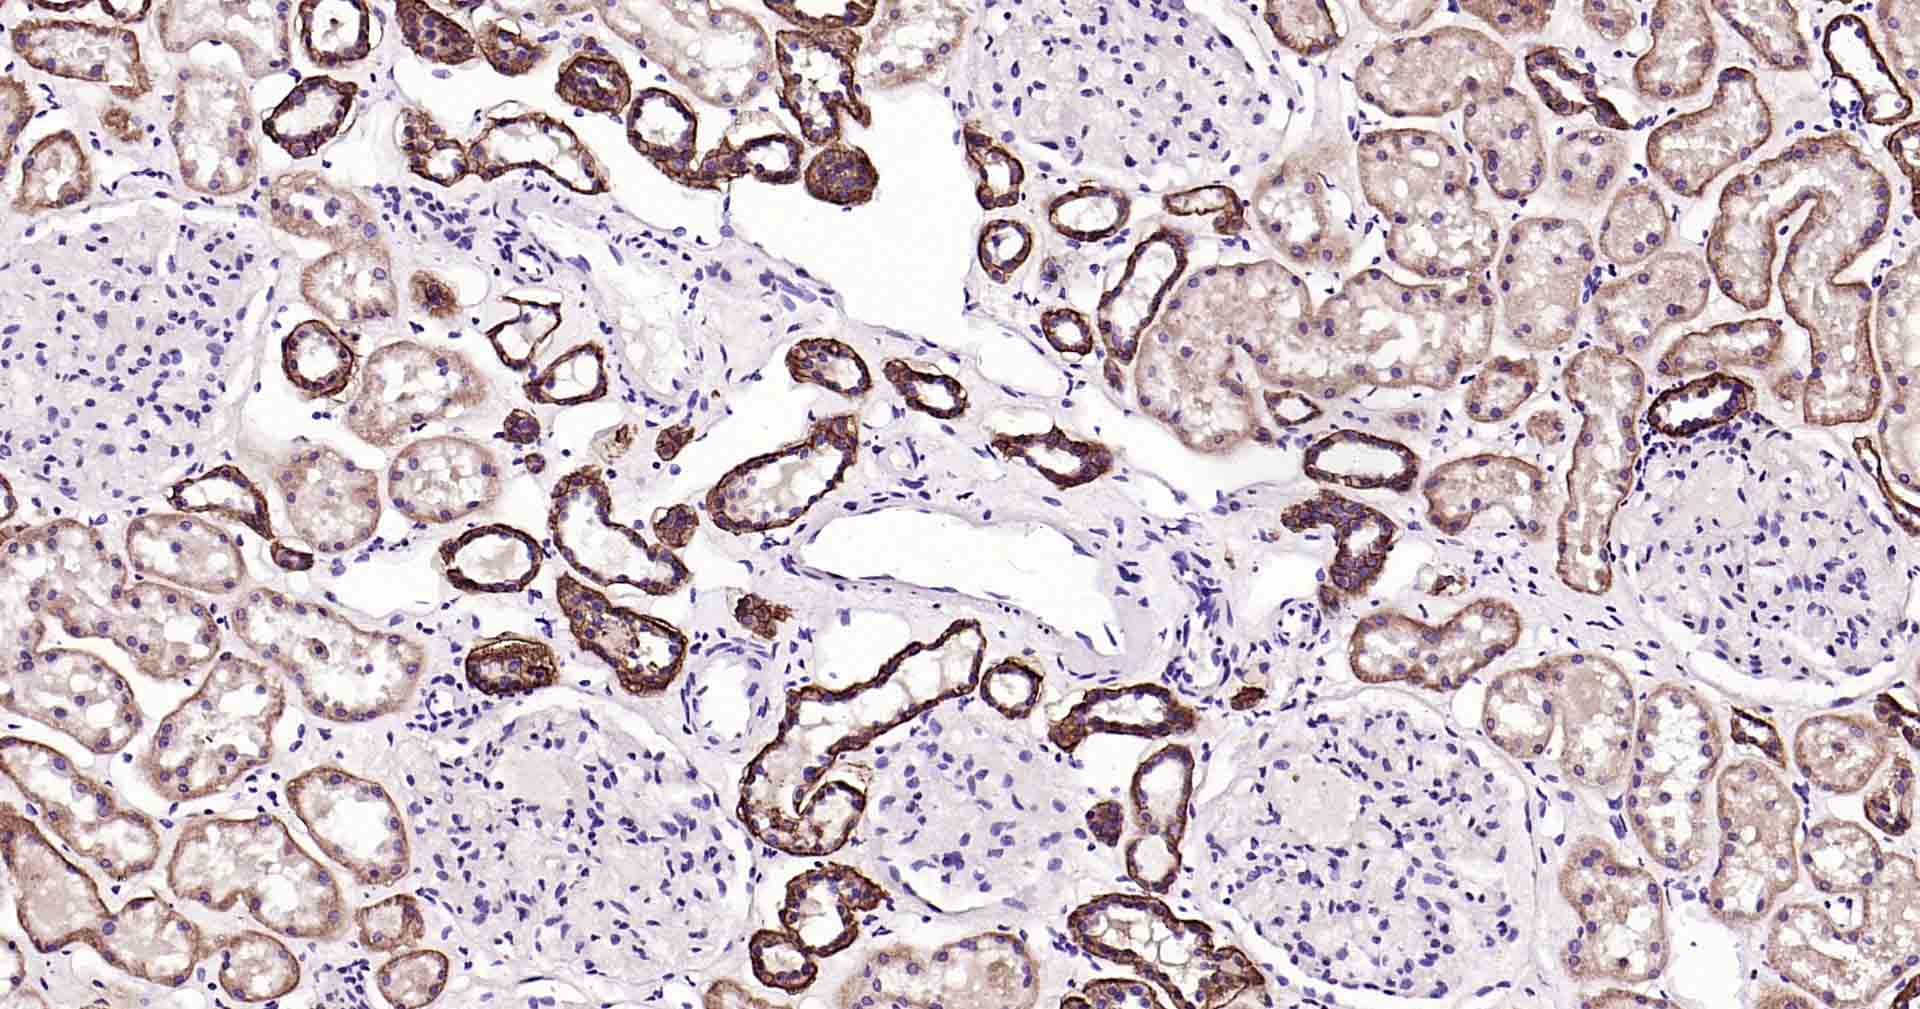

Paraformaldehyde-fixed, paraffin embedded Human Kidney; Antigen retrieval by boiling in sodium citrate buffer (pH6.0) for 15 min; Antibody incubation with ATP1B1 Monoclonal Antibody, Unconjugated(bsm-61065R) at 1:100 overnight at 4°C, followed by conjugation to the SP Kit (Rabbit, SP-0023) and DAB (C-0010) staining.

Paraformaldehyde-fixed, paraffin embedded Rat Kidney; Antigen retrieval by boiling in sodium citrate buffer (pH6.0) for 15 min; Antibody incubation with ATP1B1 Monoclonal Antibody, Unconjugated(bsm-61065R) at 1:100 overnight at 4°C, followed by conjugation to the SP Kit (Rabbit, SP-0023) and DAB (C-0010) staining.

Paraformaldehyde-fixed, paraffin embedded Mouse Kidney; Antigen retrieval by boiling in sodium citrate buffer (pH6.0) for 15 min; Antibody incubation with ATP1B1 Monoclonal Antibody, Unconjugated(bsm-61065R) at 1:100 overnight at 4°C, followed by conjugation to the SP Kit (Rabbit, SP-0023) and DAB (C-0010) staining.